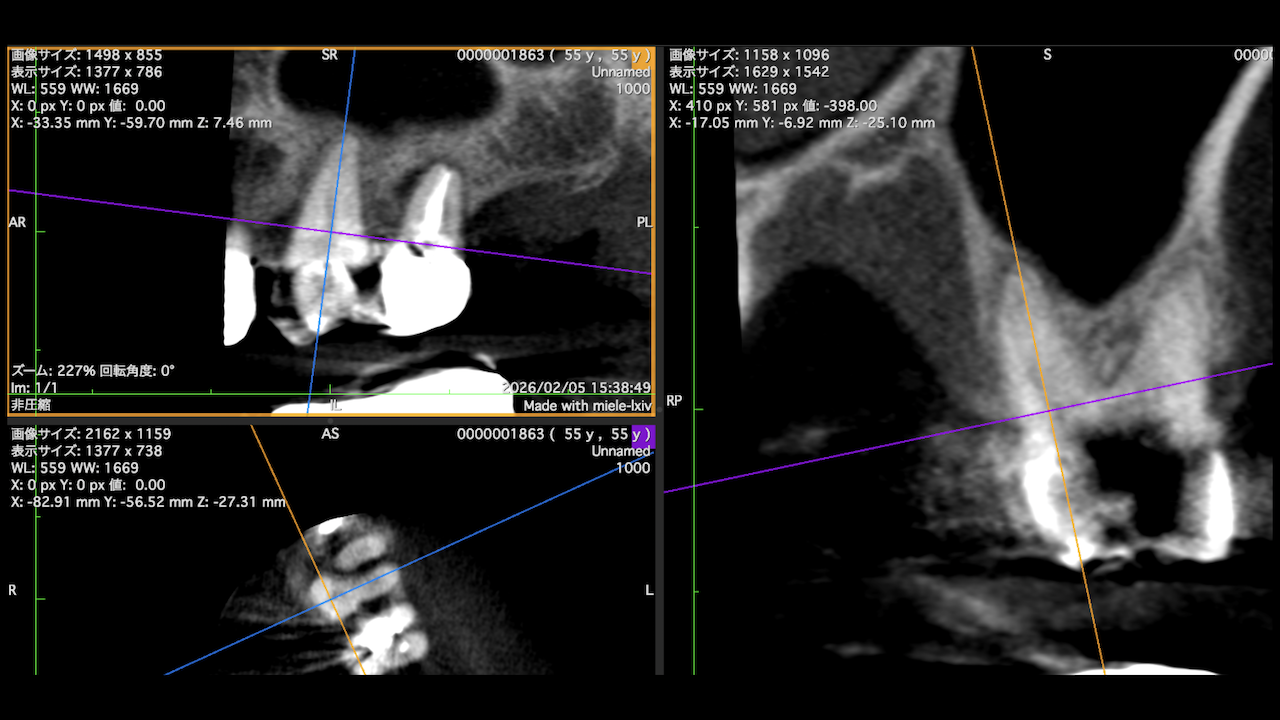

Implant近傍の#12,14に問題があるようだ。

それぞれ再根管治療した。

5ヶ月後にRecallすると、

#12,#14 MBの根尖病変は消失した。

これも非外科的歯内療法の威力が現れたケースだ。

だが、まだ4ヶ月である。

この後も問題が起きるかもしれない。

その時に解決策になるのは外科治療しかないのである。